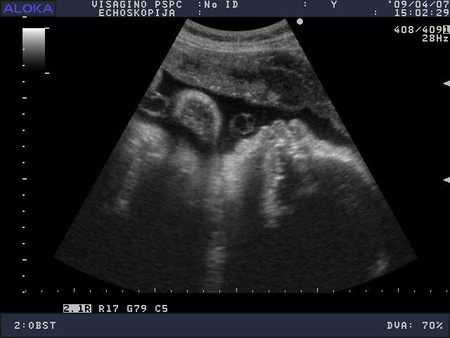

Во наша красотка, вон как губки выставила....это она всё узи водичку глотала, моя хорошая

А она такая щекастенькая, такая губастенькая. Узистка сказала, что в 3,500 кг не уложусь, 4 кг точно будет. А я так надеялась родить маленького ребёночка, чтоб легче было. Но видать придётся поднапречся ))))). Ещё сказали, что т.к. девочки рождаются раньше, то остался мне месяцок, надеюсь так и будет.

Ещё у нас пуповина возле шейки лежит, ну надеюсь, не обкрутится за месяц.